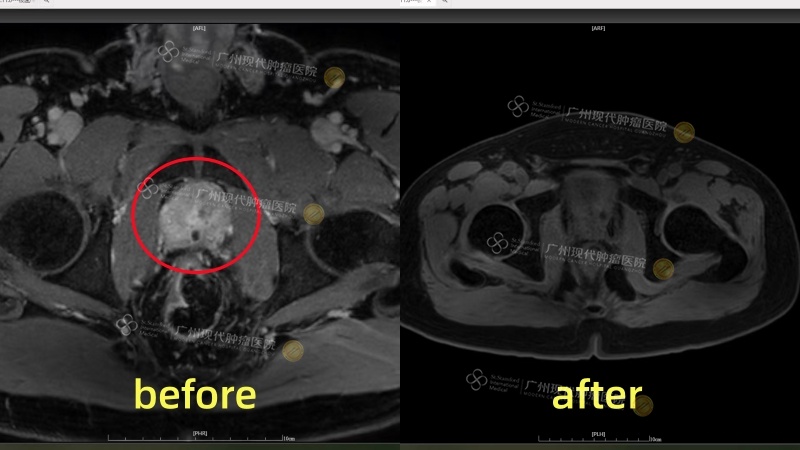

Setelah kembali ke negaranya, ia menjalani pemeriksaan ulang secara berkala. Setiap kali melihat penurunan kadar PSA, rasa percaya dirinya semakin meningkat. Hasil MRI terbaru menunjukkan bahwa tumor telah mengecil secara signifikan, hampir menghilang. “Yang paling saya syukuri adalah saya tidak mengalami inkontinensia urin dan tidak ada fungsi tubuhku yang terganggu. Saya masih diri saya yang dulu, hanya saja kini tubuhku tak lagi menyembunyikan ‘bom waktu’,” katanya dengan suara tenang namun sedikit bergetar. Pengobatan itu tidak hanya menekan sel-sel kanker, tetapi juga menjaga tanggung jawab dan martabatnya sebagai seorang ayah dan suami.

Setelah menjalani pengobatan minimal invasif, tumor prostat berukuran sekitar 3cm telah hampir “sepenuhnya menghilang”